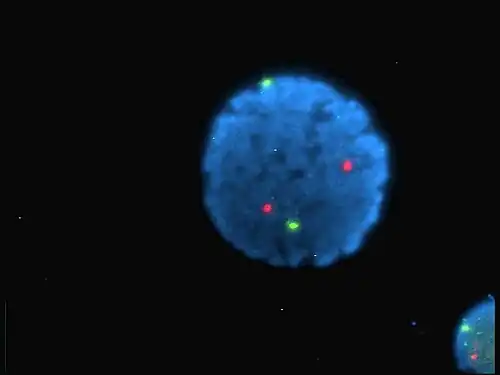

Human lymphocyte nucleus stained with DAPI with chromosome 13 (green) and 21 (red) centromere probes hybridized (Fluorescent in situ hybridization (FISH)) -